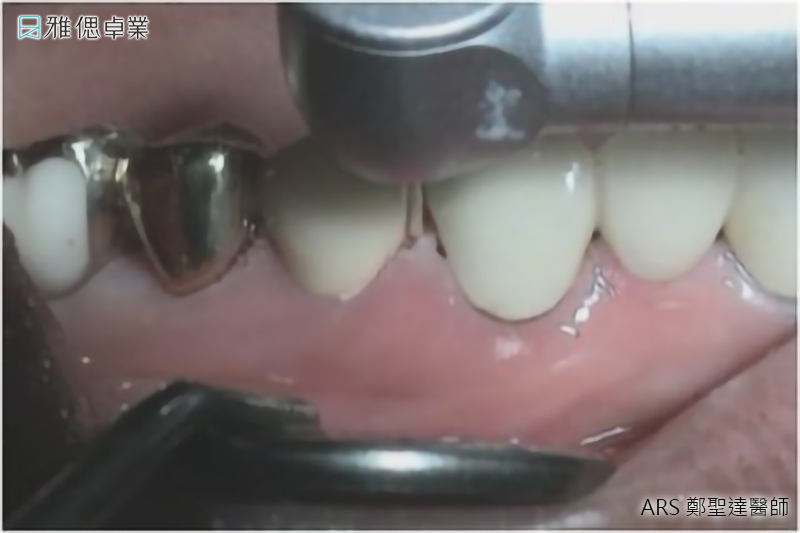

實際案例水雷射牙冠增長術術前術後對照